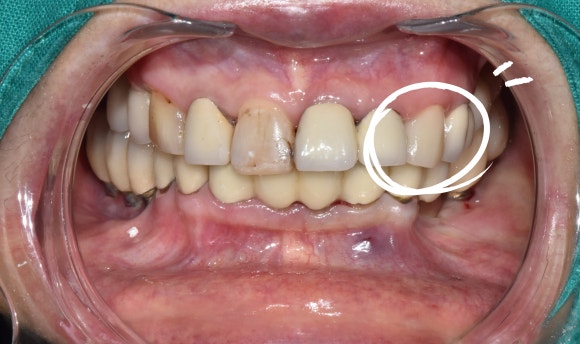

아래 사진은 기나긴 치과 여정 끝에 저를 만나셔서

오른쪽 위 임플란트를 진행 중이신 환자분이십니다.

하얗게 보이는 치아들이 크라운으로 씌운 치아인데요,

엑스레이만 봐서는 크라운 하방에 충치가 있는지 없는지 알 수가 없습니다.

다 멀쩡해보이는데요??

화살표가 가르키는 치아를 봐주세요.

크라운과 치아 사이의 경계가 깨~끗합니다.

그!러!나!

잇몸치료를 위해 마취를 하고 치석을 박박 긁어내던 순간......!!

크라운 하방에 기구가 걸리는 것이 느껴집니다.

구강카메라로 즉시 확인해보니,

아뿔싸,

치태와 치석 아래 숨어있던 충치가

이제야 모습을 드러내네요.